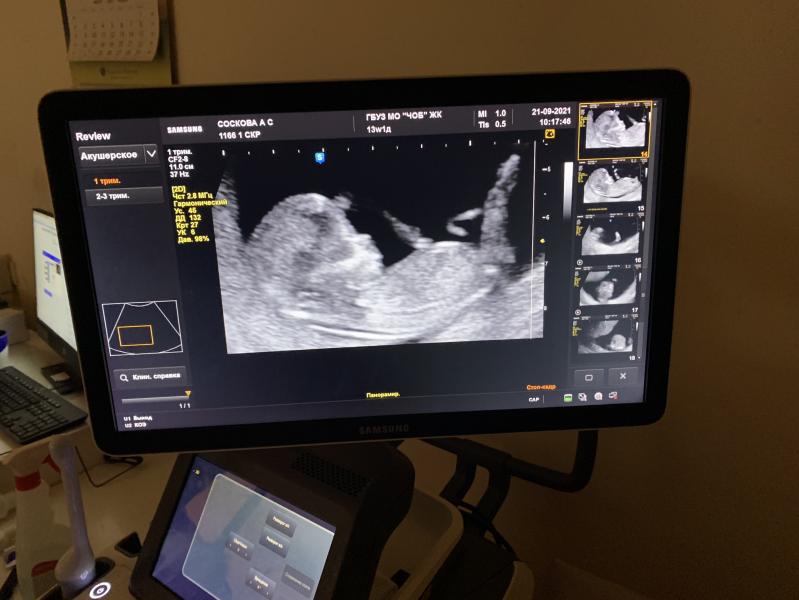

А вот и наша первая фотография 😍

Малыш очень сильно активничал у меня в животе , дергал ручками и ножками , узистка к сожалению только так разрешила сделать фото , пол ещё не знаем (на какой неделе вы узнали пол малыша ?) я вот думаю платно сходить через недельки 4 , но вот покажет ли узи или рано ещё будет ?